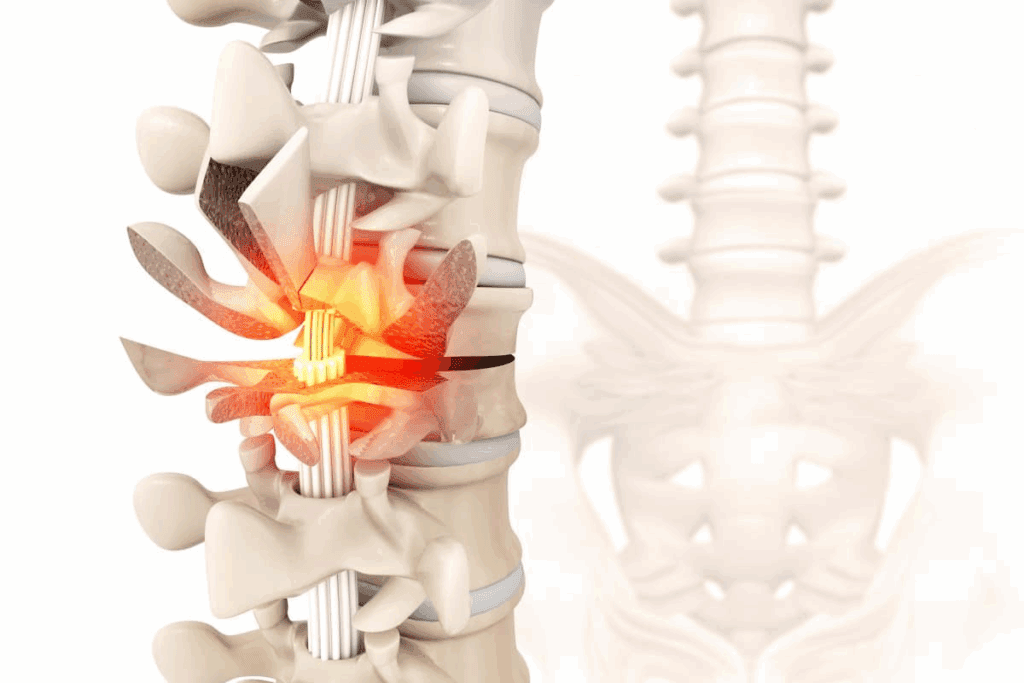

Vertebral compression fractures, often from osteoporosis, can hurt a lot and limit your movement. We explain how kyphoplasty can ease the pain and make your spine stable again.

Common Causes for Spinal Compression Fractures

Spinal compression fractures can happen due to osteoporosis or injuries. Knowing why they happen helps find the right treatment. Osteoporosis is a big risk for older people.

Kyphoplasty deals with the spine, so knowing spinal anatomy is important. The spine has parts like the cervical, thoracic, lumbar, sacrum, and coccyx. Kyphoplasty mainly focuses on the thoracic and lumbar areas.

T12 and L1 are specific vertebrae in the spine. T12 is the twelfth thoracic vertebra, and L1 is the first lumbar vertebra. These are common sites for fractures, making them key for kyphoplasty.